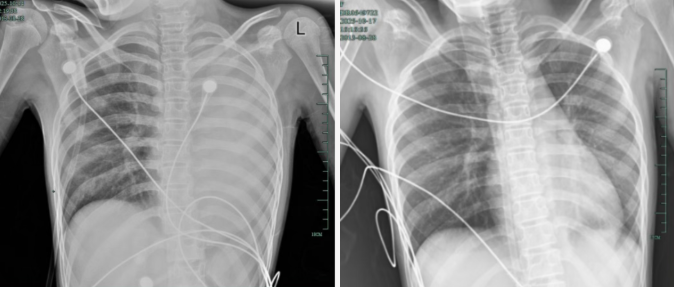

治疗前后影响对比,左肺从“白肺”到正常状态。

什么病?如此来势汹汹?

孩子感冒咳嗽看似常见,可12岁女孩笑笑(化名)的经历却让人感到后怕——仅发热1天,左肺就变成了 “白肺”,呼吸急促到无法平躺,血氧饱和度勉强维持在90%左右,情况十分危急!